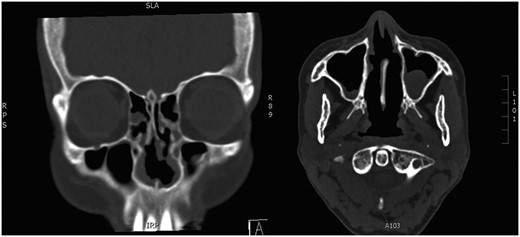

A biopsy of the inferior turbinate undertaken elsewhere reportedly showed benign cartilage and reactive looking bone. Computerized tomography (CT) of paranasal sinuses described hypertrophic bony change confined to the inferior and middle turbinates bilaterally and a deviated septum to the left. The radiological features were suggestive of a benign enchondroma involving both inferior turbinates (Fig. 1). The patient underwent endoscopic inferior turbinectomies in order to achieve a patent nasal airway. A combination of curetting and fracturing of the abnormal bone was required to achieve this. Throughout the dissection, bony adhesions were noted to the septum that needed to be divided to aid in removing the inferior turbinate. An absorbable dressing was placed with the patient instructed to perform regular saline nasal douching during the postoperative period.

Preoperative CT. Paranasal sinuses (coronal and axial) showing bilateral inferior turbinate tumour.